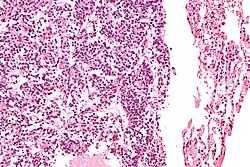

Typical pulmonary carcinoid tumour

| Micrograph of a typical pulmonary carcinoid tumour. | |

The definitive diagnosis is rendered by a microscopic examination, after excision. Typical carcinoids have cells with stippled chromatin and a moderate quantity of cytoplasm. They typically have few mitoses and lack necrosis. By definition, they are greater than 4 mm in largest dimension; smaller lesions are referred to as pulmonary carcinoid tumourlets.